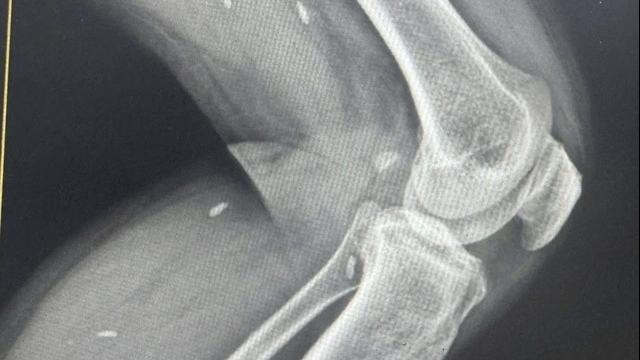

| Nhà nuôi bệnh nhân sẽ không bị thu tiền chăm sóc người bệnh (ảnh minh họa) |